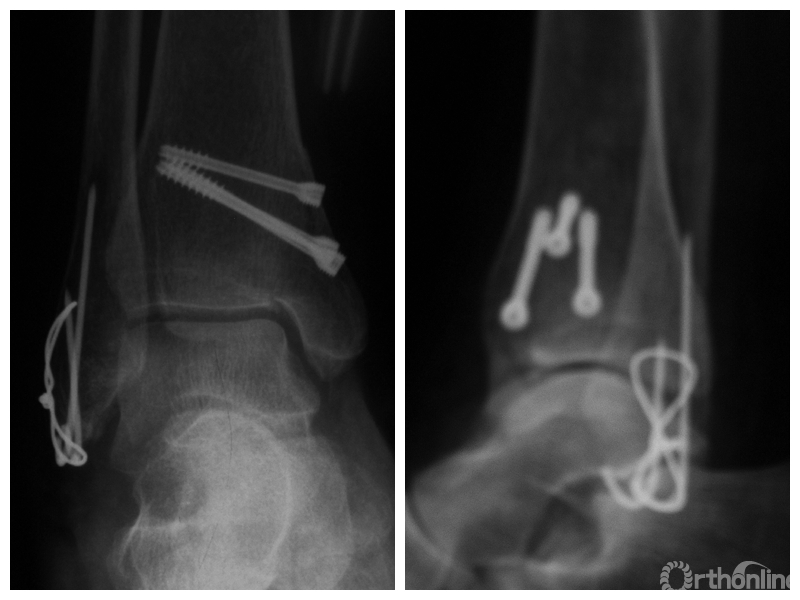

图1 支撑钢板固定组患者,女,63岁,右侧旋后-内收型II度踝关节骨折 a. 术前正侧位X线片;b. 术前CT;c. 术后2周正侧位X线片;d. 术后2年正侧位X线片

图1c 术后2周正侧位X线片

两组患者均获随访,支撑钢板固定组随访时间46~91,平均64.5个月;螺钉固定组随访时间44~86,平均59.5个月。支撑钢板固定组患者术后完全负重时间为(11.5±1.6)周,较螺钉固定组的(12.6±2.3)周显著缩短,比较差异有统计学意义(t=2.05,P=0.04)。X线片复查示,支撑钢板组均获解剖复位,均达愈合;螺钉固定组有20例获解剖复位,2例畸形愈合,1例不愈合,支撑钢板组骨折愈合时间为(11.5±1.6)周,螺钉固定组为(12.0±1.7)周,比较差异无统计学意义(t=1.06,P=0.30)。见图1、2。支撑钢板固定组3例(10%)、螺钉固定组4例(17.4%)发生创伤性关节炎,均采取保守治疗;两组比较差异无统计学意义(P=0.45)。